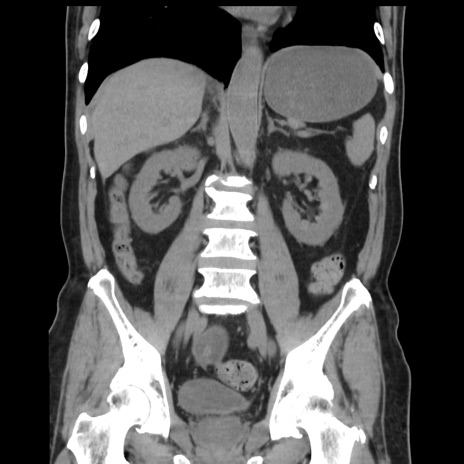

症例16(冠状断像)

【症例】 70歳代男性

【主訴】 腹痛、嘔吐

【現病歴】 約1ヶ月前より間欠的に腹痛と嘔吐あり、当院消化器内科を受診したところCTで多発する肝臓のLDAを指摘され、精査中であった。以降は消化器症状は安定していたが、2日前より嘔気と腹痛があり、同日より排便・排ガスが消失した。改善認めず、 本日、救急外来を受診した。

【身体所見】意識清明・会話良好、BT 36.3℃、BP 127/80mmHg、 P 80bpm、腹部:膨満あり、平坦・軟、上腹部正中および下腹部正中に圧痛あり、反跳痛なし、筋性防御なし。

【データ】WBC 7200、CRP 0.77